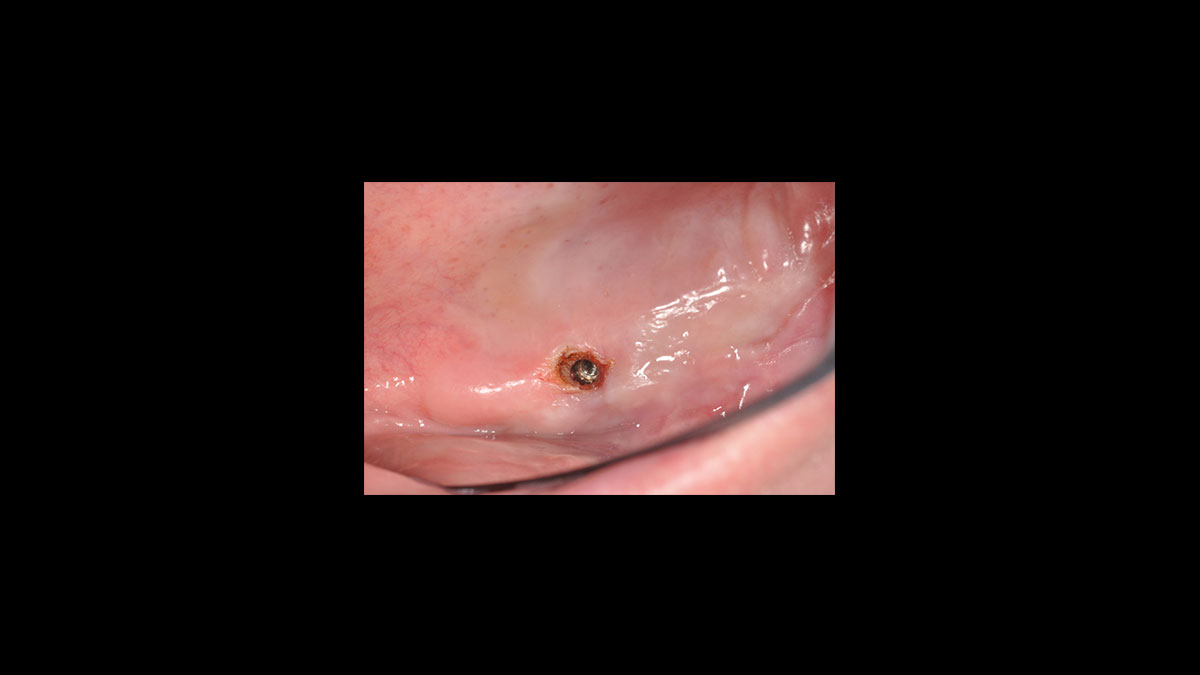

Exposition de l’implant